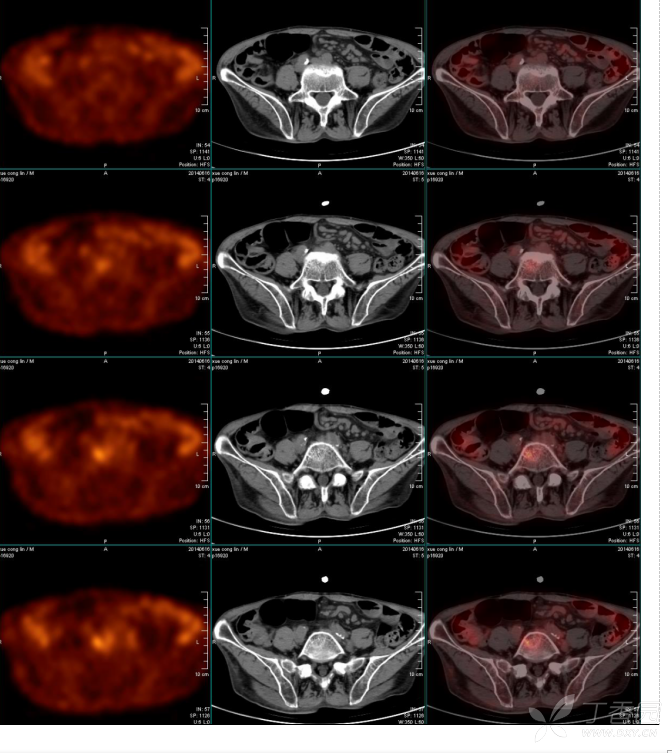

petct片子

这么夸张的 pet-ct 的检查结果,广泛的软组织转移.

pet-ct:淋巴瘤? - 影像医学和核医学讨论版 -丁香园论坛

图片尺寸672x753